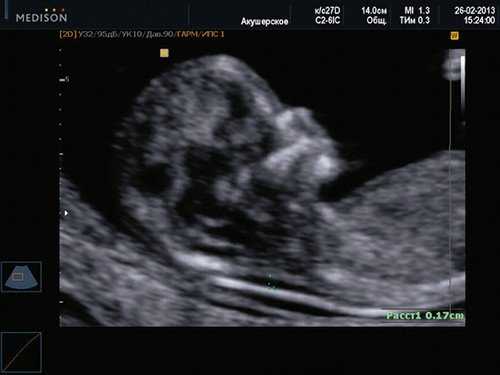

Картина пренатального УЗИ в 35 недель гестации: форма головы аномальная (клубникообразная). Кости при надавливании датчиком не деформируются. Расширение боковых желудочков, передние рога до 10 мм справа и слева. Полость прозрачной перегородки до 9,9 мм. Задние рога - 11 мм, слева - 12 мм. Отмечено расширение IVжелудочка до 12 мм. Имеется гипоплазия червя мозжечка, расширение большой цистерны до 12 мм.

Картина нейросонографии в первые сутки жизни: в задней черепной ямке при коронарных и сагиттальном сканированиях наблюдается крупное анэхогенное («кистовидное») образование, включающее расширенные III и IV желудочек; полушария мозжечка резко уменьшены, червь не определяется; мозжечковый намет смещен вверх.